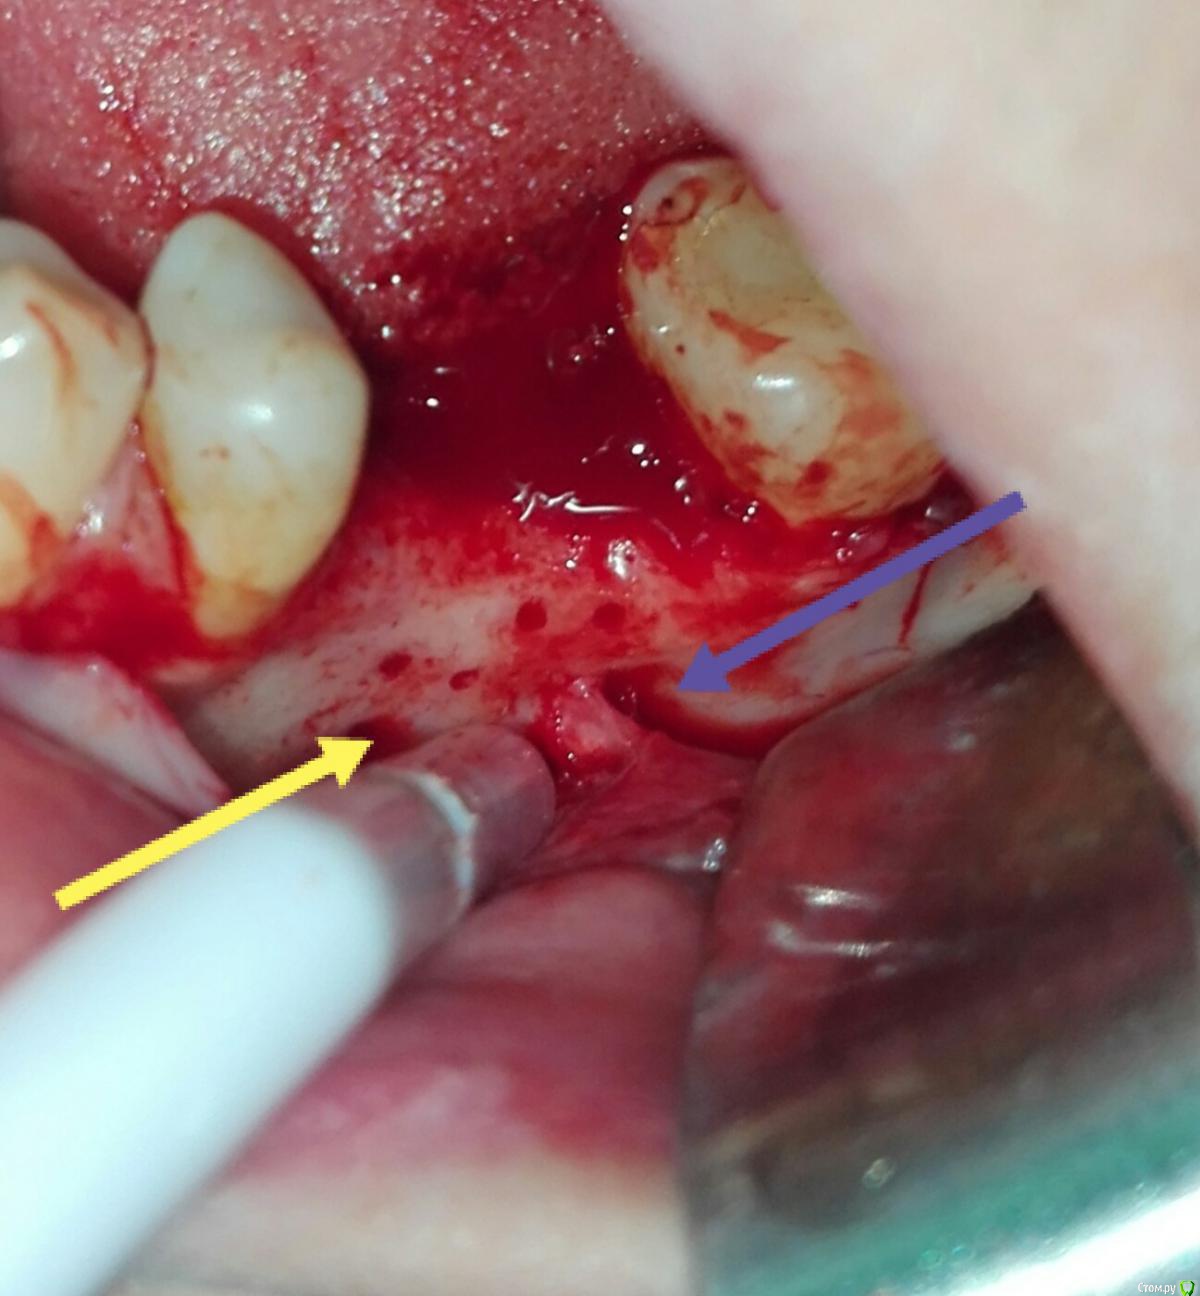

karasov Опубликовано 20 октября, 2016 Поделиться Опубликовано 20 октября, 2016 (изменено) В области 36 работал с ламиной. Наткнулся на нерв. Причем два. Один обошел , второй нет. Что ждать?на кт ееееле заметны Изменено 20 октября, 2016 пользователем karasov Ссылка на комментарий

kriokov Опубликовано 21 октября, 2016 Поделиться Опубликовано 21 октября, 2016 Наткнулся на нерв. не похож на нерв. имхо. Ссылка на комментарий

karasov Опубликовано 21 октября, 2016 Поделиться Опубликовано 21 октября, 2016 не похож на нерв. имхо.По кт есть однозначно связь с нижним альвеолярным. Визуально на сосуд не похоже Ссылка на комментарий

karasov Опубликовано 21 октября, 2016 Поделиться Опубликовано 21 октября, 2016 Слева был, справа есть Ссылка на комментарий

karasov Опубликовано 21 октября, 2016 Поделиться Опубликовано 21 октября, 2016 Обычно встречается первый тип, но у части населения бывает и второй..Или третий Ссылка на комментарий